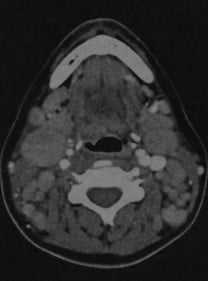

Неходжкинская лимфома. КТ с контрастированием: множественные лимфатические узлы под нижней челюстью и около яремной вены, а также позади грудино-ключично-сосцевидной мышцы. Узлы имеют овальную или округлую форму, повышенную плотность по сравнению с окружающими мышцами, после введения контраста наблюдается гомогенное усиление.